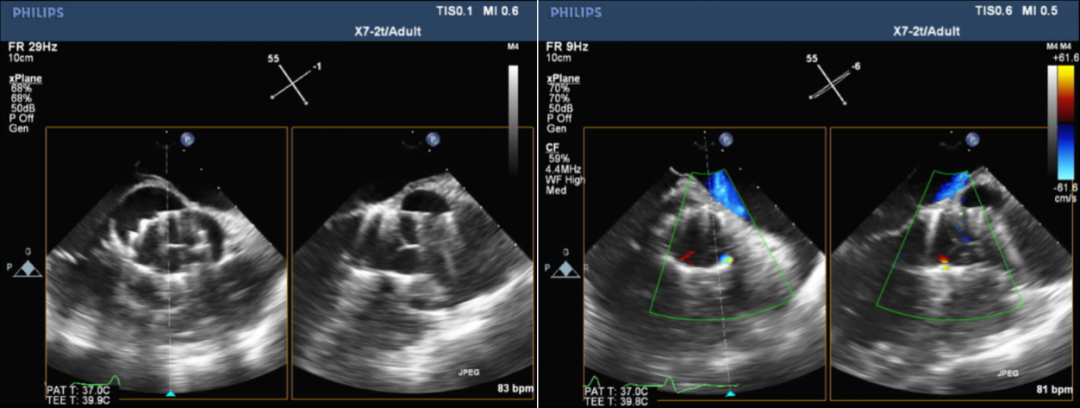

术前超声:

术前超声提示:

二叶式主动脉瓣(TYPE1)关闭不全并钙化;主动脉窦部瘤样增宽;左室大;主动脉硬化;主动脉瓣上血流速度加快,瓣下返流(大量)。

术后超声:

Vitaflow瓣膜位置良好,轻微瓣周漏